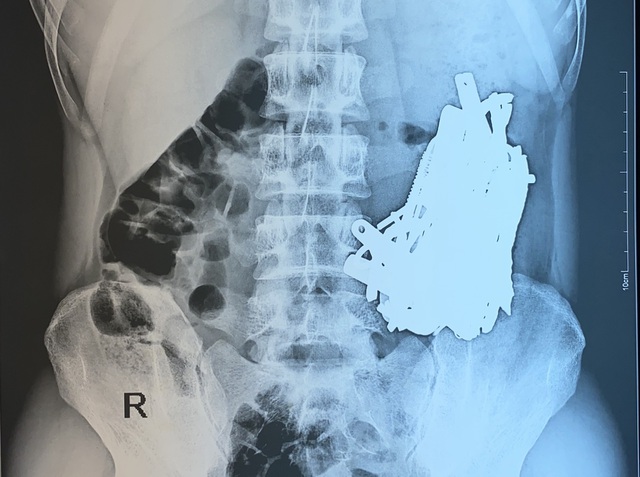

Hình ảnh kiểm tra cho thấy, dị vật cản quang xếp đầy trong đường tiêu hóa của bệnh nhân

Trên kết quả kiểm tra hình ảnh, bác sĩ cũng "tá hỏa" khi phát hiện dạ dày bệnh nhân chứa đầy các vật cản quang có hình dạng khác nhau. Dị vật chất đầy trong dạ dày người bệnh nên không thể lấy ra bằng phương pháp nội soi. Ngay lập tức, bác sĩ chỉ định phẫu thuật cấp cứu cho bệnh nhân.

Bằng phương pháp mổ hở, bác sĩ đã mở ổ bụng, mở dạ dày lấy ra khoảng 1kg sắt thép các loại như đinh, thìa, bấm móng nay, lưỡi dao, thỏi sắt, móc đồ… đã bị dịch dạ dày ăn mòn. Do số lượng dị vật trong bụng bệnh nhân quá nhiều nên ê kíp phải tiến hành chụp C-ARM ( X-quang trong mổ) để tránh bỏ sót dị vật.